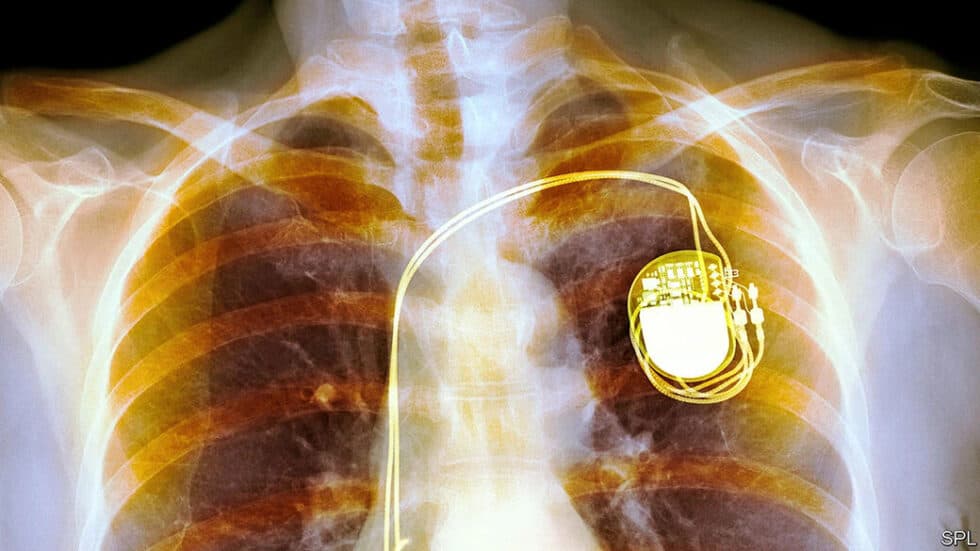

Pacemakers are small, sophisticated electronic devices that play a critical role in maintaining a regular, effective heartbeat in patients whose natural cardiac rhythms are disrupted or insufficient. Essentially, a pacemaker is implanted surgically under the skin, typically just below the collarbone, with one or more thin wires called leads connecting it to the heart. These leads deliver precisely timed electrical impulses that prompt the heart muscle to contract, ensuring it beats at a normal rate and rhythm. This device is especially valuable for individuals suffering from conditions such as bradycardia, where the heart beats too slowly, or various forms of heart block where electrical signals are delayed or obstructed. Modern pacemakers now often include advanced features like rate responsiveness, which adjusts the pacing rate in accordance with a patient’s level of physical activity, and some even offer sophisticated diagnostic capabilities for remote monitoring by physicians. They are available in several types, including single-chamber, dual-chamber, and biventricular devices, each tailored to address specific cardiac conditions. Their batteries, designed to last several years before replacement is required, ensure reliable long-term operation and reduce the need for frequent interventions.

Pacemaker implantation is indeed a surgical procedure, but it is generally not considered major surgery due to its minimally invasive nature. Typically performed under local anesthesia with light sedation, the procedure avoids the risks associated with general anesthesia and involves only small incisions. A small cut is made near the collarbone to create a pocket under the skin where the pacemaker device is placed, and one or more thin leads are inserted through a vein into the heart. Using real-time imaging techniques, the surgeon precisely positions these leads to monitor and regulate the heart’s rhythm, ensuring the device functions as a seamless extension of the heart’s electrical system. The entire process usually takes one to two hours, and thanks to its minimally invasive approach, most patients can return home the same day or after a brief overnight stay for observation.